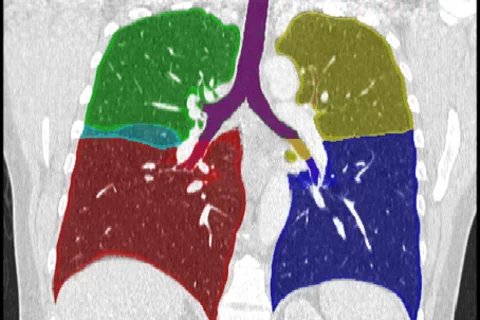

Chronic obstructive pulmonary disease (COPD) is the fourth leading cause of death in the United States. In 2018 the FDA approved endobronchial valves (EBV) as a Breakthrough Device for endobronchial lung volume reduction in the treatment of severe emphysema. The goal of this project is to develop more robust and quantitative criteria, a CT imaging biomarker, to identify patients that are likely to benefit from EBV implantation. CVIB scientists were awarded an R01 grant from the NIH to support the translational software development, led by Mike McNitt-Gray, with co-Principal Investigators Grace Kim, Jonathan Goldin, and Matt Brown. The computer vision system will analyze chest CT scans to quantitatively assess heterogeneity of emphysema and fissure completeness, markers of effective treatment. The funding awarded to support this imaging biomarker translation to clinical practice totals around $1.5M over a 4-year period to support scientists, staff, and students involved in the research.